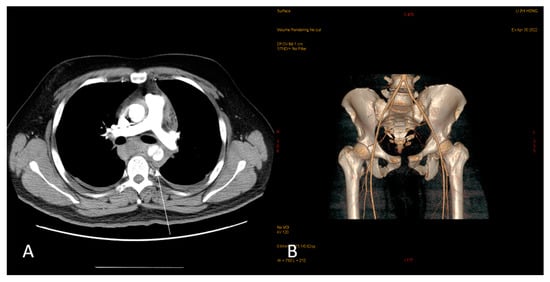

2. Case Report